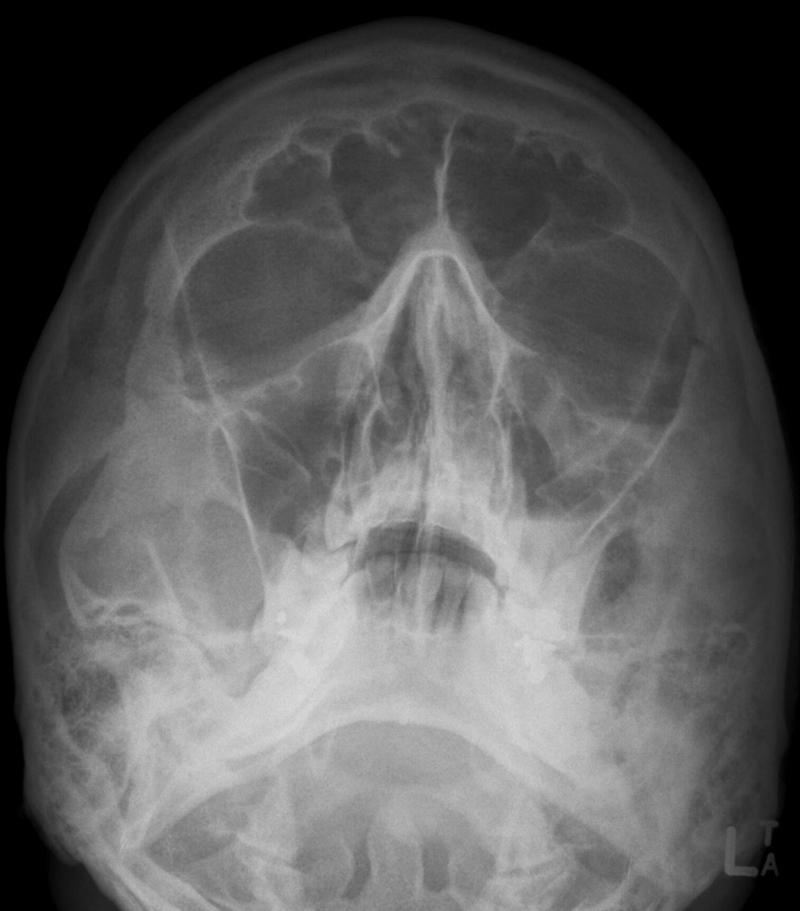

Orbital Floor Fracture